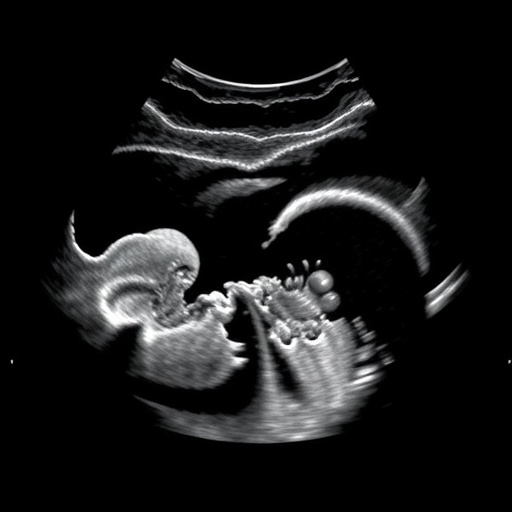

In a groundbreaking study published in Nature Biomedical Engineering, researchers have unveiled an innovative approach to interpreting fetal ultrasound images through the application of a visually grounded language model. This state-of-the-art technology aims to revolutionize the way medical professionals understand complex ultrasound data, enhancing both diagnostic accuracy and patient care.

The study, led by a team of experts including Guo, Alsharid, and Zhao, presents a sophisticated algorithm designed to analyze visual input from ultrasound scans and contextualize it within a linguistic framework. This model effectively bridges the gap between linguistic representations and visual data, enabling a deeper understanding of fetal development and health indicators.

One of the primary challenges in interpreting ultrasound images lies in the vast amount of information conveyed through subtle visual nuances. The model’s ability to translate these visual cues into coherent narrative descriptions is an essential advancement, paving the way for improved clinical decision-making. The researchers demonstrated that their model could provide accurate descriptions of fetal anatomy, positioning, and even potential anomalies, all of which are critical for timely medical interventions.